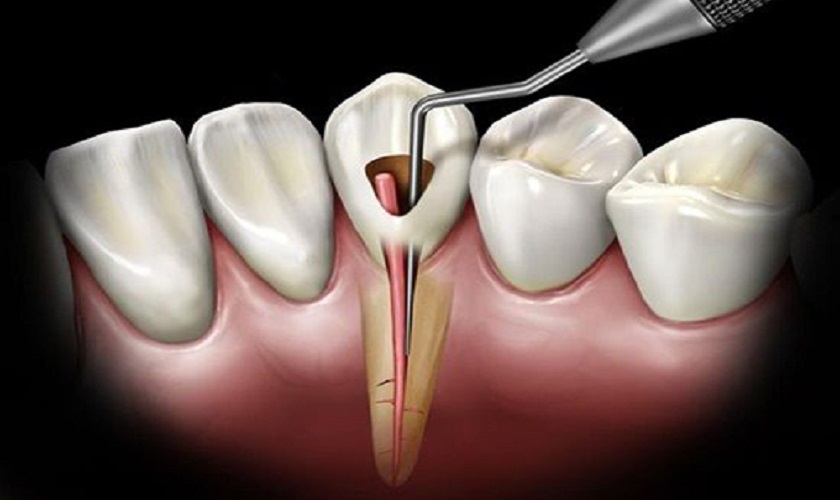

Diệt tủy răng

Bằng cách sử dụng mũi khoan chuyên dụng, bác sĩ sẽ tạo một đường nhỏ thông từ bề mặt răng tới ống tủy. Tiếp theo là mở tủy, tính toán chiều dài ống tủy và hút sạch các mô tủy đã bị hoại tử, viêm nhiễm.

Sau khi lấy hết lượng tủy răng bị hỏng ra, bác sĩ sẽ vệ sinh và điều chỉnh lại hình dáng ống tủy.

Các mô tủy bị viêm nhiễm, hoại tử cần được hút sạch hoàn toàn